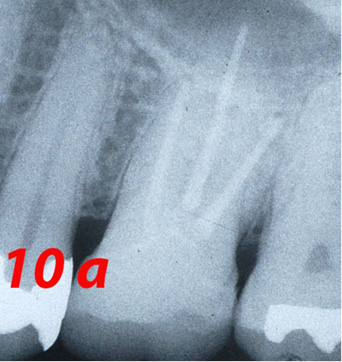

At the time of the examination, 10 (90.9%) ECs were in function in 10 patients. One EC had been lost after 12 years and 9 months due to periodontal disease in tooth #26. No restoration had loosened. Neither secondary caries nor radiographic failures were observed in the 10 PETT in function (Figs. 1a,1d; 2c; 3c,3d; 4c).

Fig. 1d X-ray control after 9 years.

Fig. 4c X-ray control after 10 years (a=years).